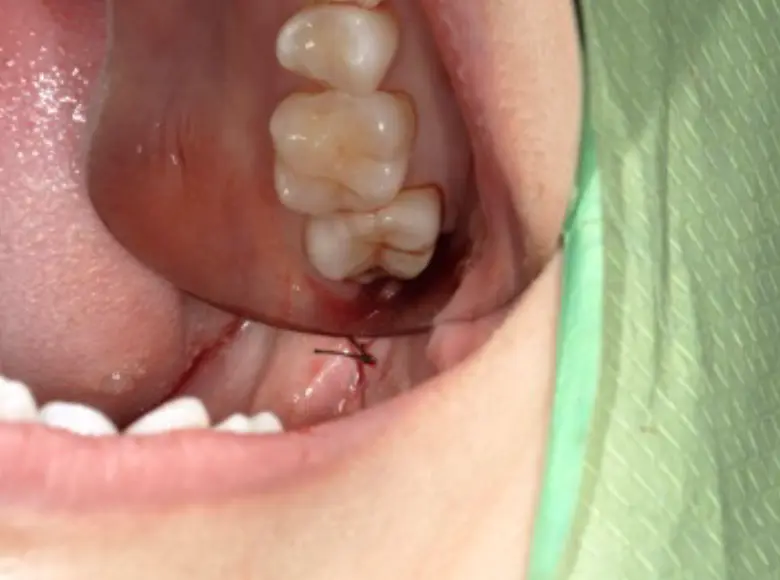

症例03

| 主訴・病名 | 親知らずが気になる・抜きたい、半埋伏智歯 |

|---|---|

| 年齢・性別 | 25歳・男性 |

| 治療期間 | 2日(当日抜歯、抜糸)、処置時間9分 |

| 治療費 | 7,350円(初診、CT) |

| 治療内容 | 局所麻酔下で下顎半埋伏智歯抜歯。 |

| 担当医 | 鈴木 |

| 治療のリスク | 手前の歯がセラミックの被せ物 → 破折リスクがあるも無傷。開口障害で器具が届きにくいが短時間で処置。 |